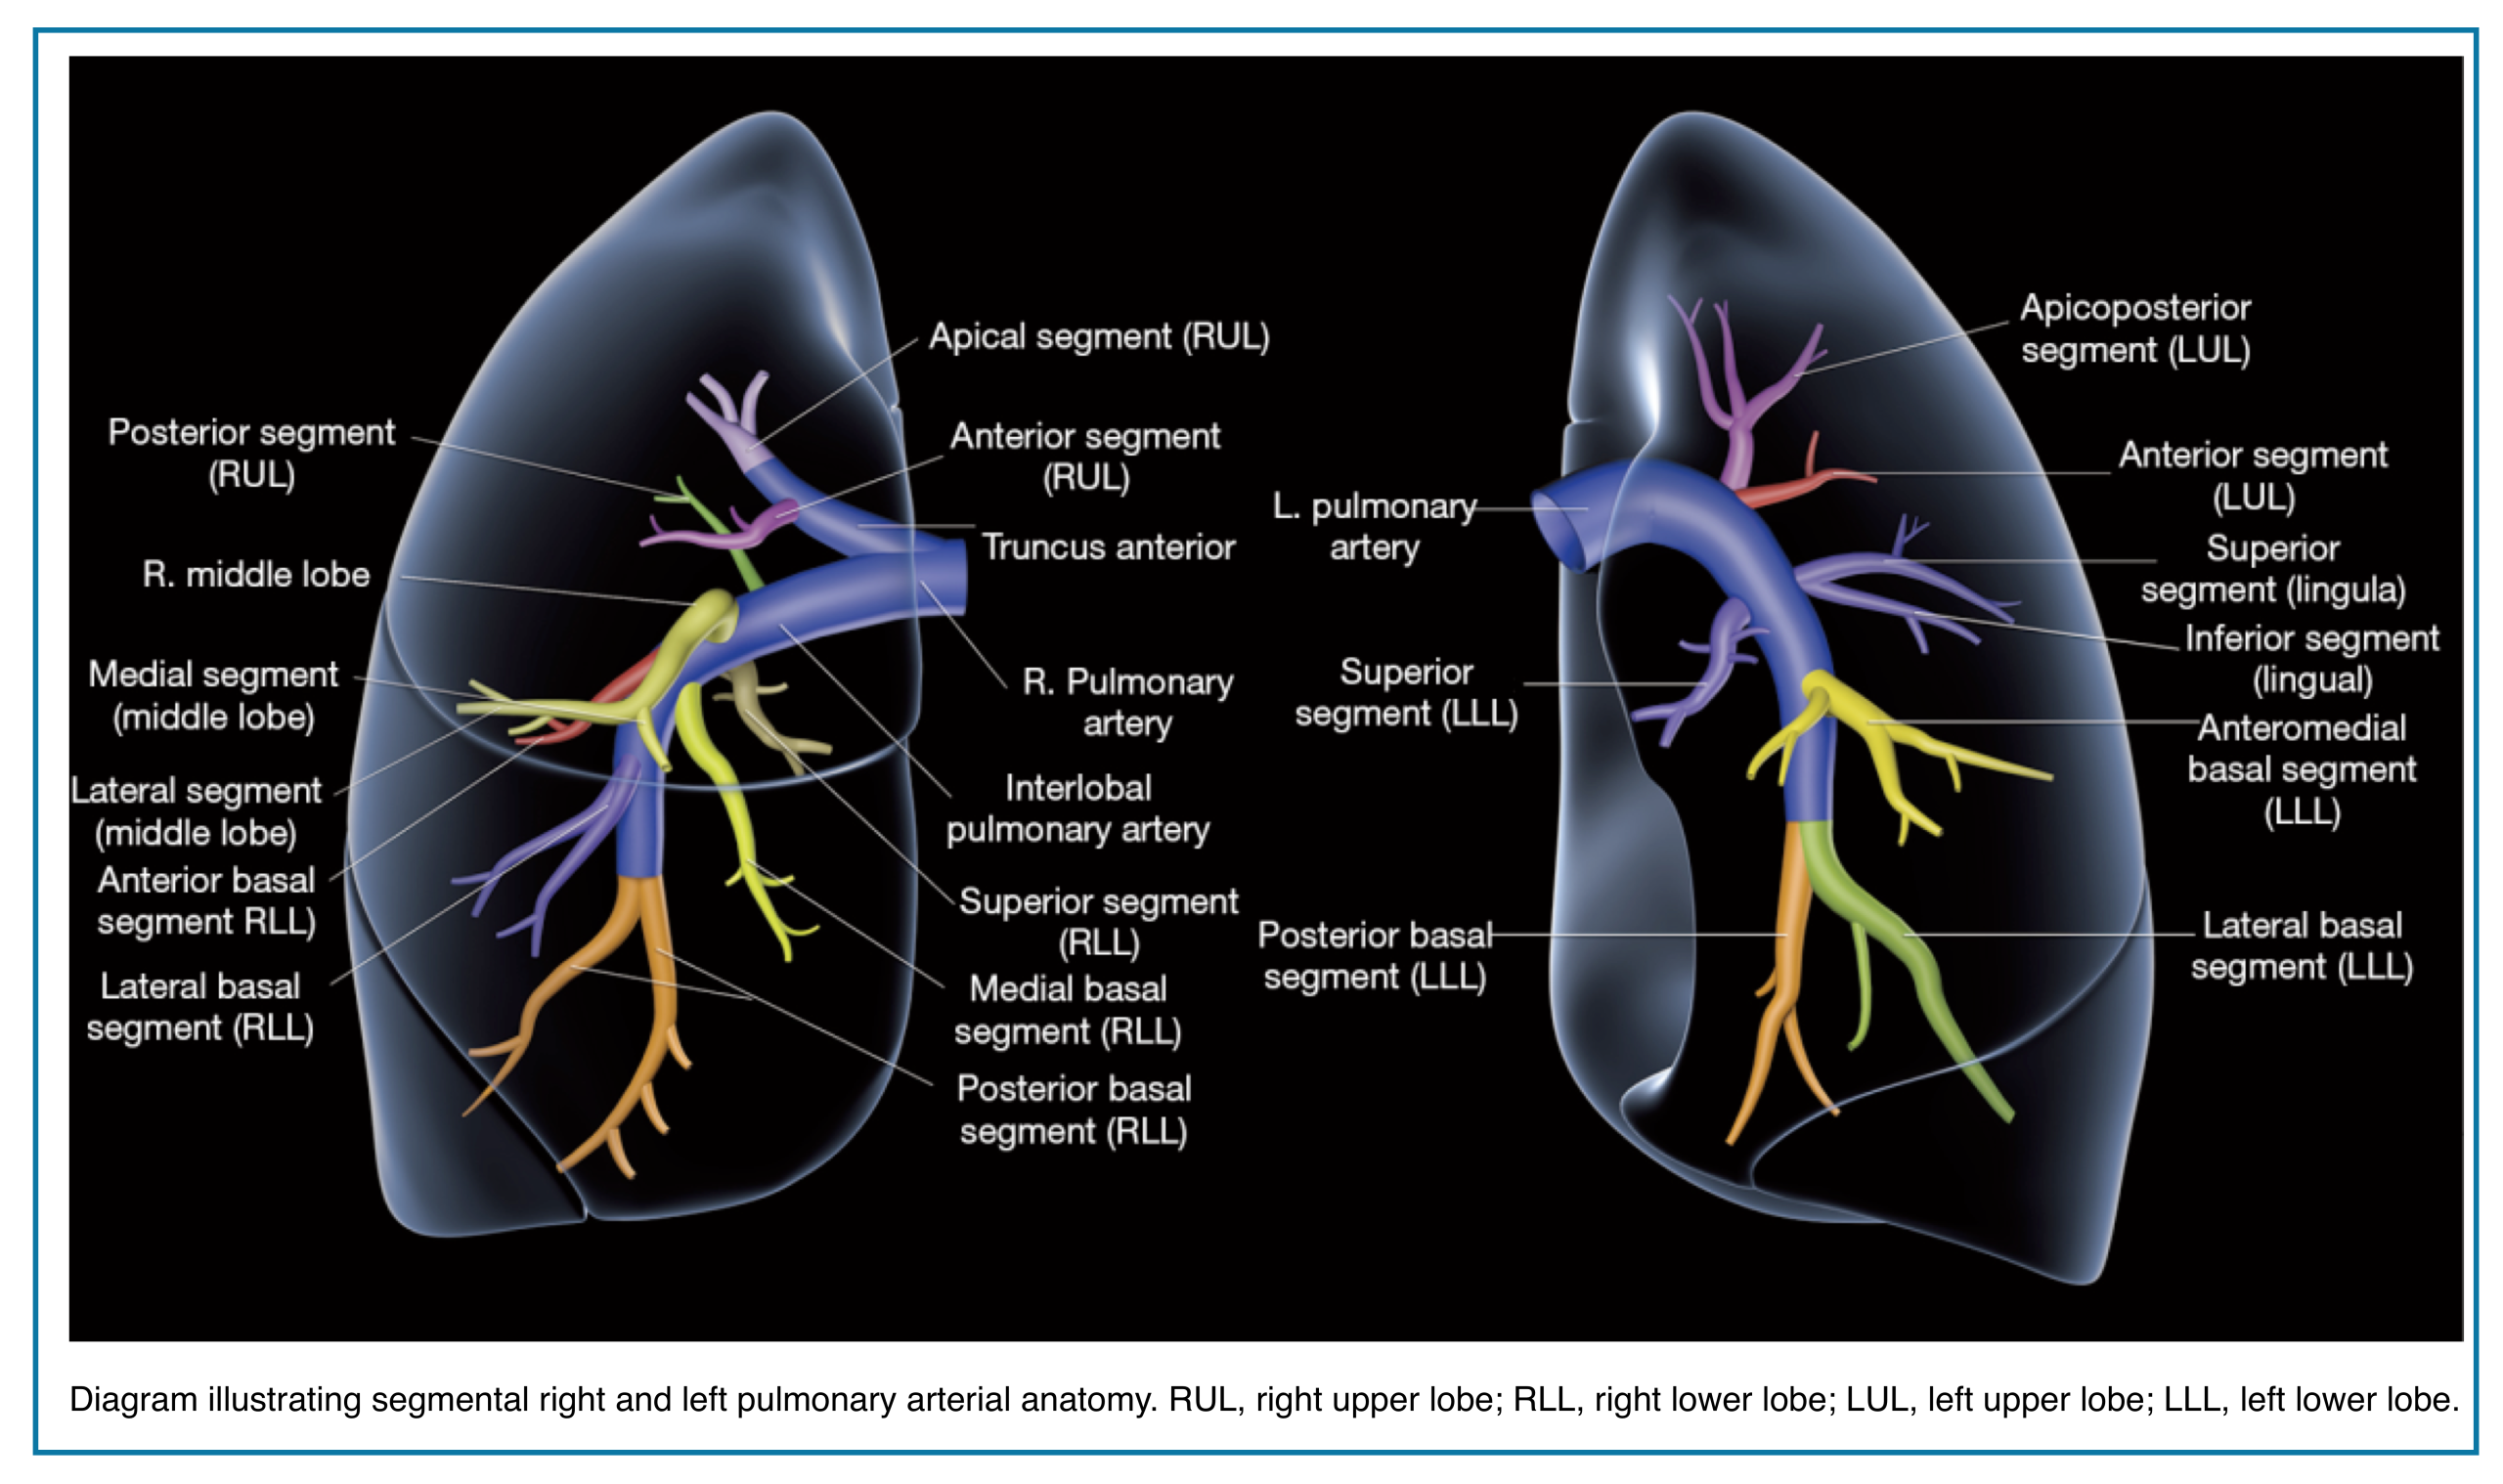

Applied anatomy

- The pulmonary trunk (aka. main pulmonary artery “MPA”) is the sole arterial output from the right ventricle (figure below).

- At the level of the 5th thoracic vertebral body plane, the MPA divides into the right and left pulmonary.

- The right and left pulmonary arteries divide into two lobar branches each, and subsequently into segmental and sub-segmental branches.

-

- Right pulmonary artery

- It gives rise to two branches: the truncus anterior and the interlobar pulmonary arteries.

- Truncus anterior is the 1st branch (ascending) that supplies the right upper lobe.

- The interlobar pulmonary artery runs inferiorly and down the right side, supplying the right middle and lower lobes.

- Left pulmonary artery

- The left pulmonary artery represents the continuation of the MPA.

- The first lobar branch gives rise to segmental arteries that supply the left upper lobe.

- The interlobar artery gives off divisions to supply the lingula and left lower lobe.

📖 Read more on this Radiology Assistant, Radiopaedia

💡 Pulmonary Artery Course: Quick Pearl

- Upper lobe arteries run central to their bronchi.

- Middle lobe, lingular, and lower lobe arteries run peripherally to their bronchi.

- Pulmonary veins usually lie anterior to the arteries, except in the right upper lobe, where venous position is more variable.